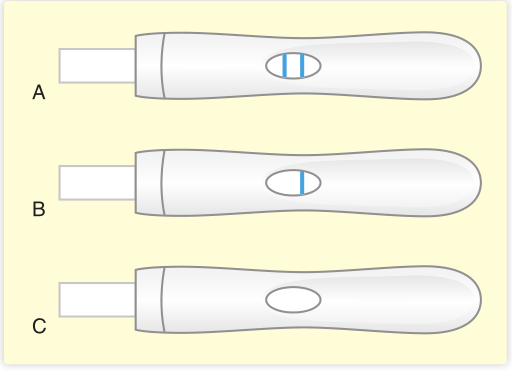

Fig 5.5显示了怀孕测试的阳性和阴性结果,以及未通过的检测(例如,当使用的尿液不足时)。

Fig 5.5 A、双线阳性妊娠试验;B、单行阴性试验;C、测试失败,无线